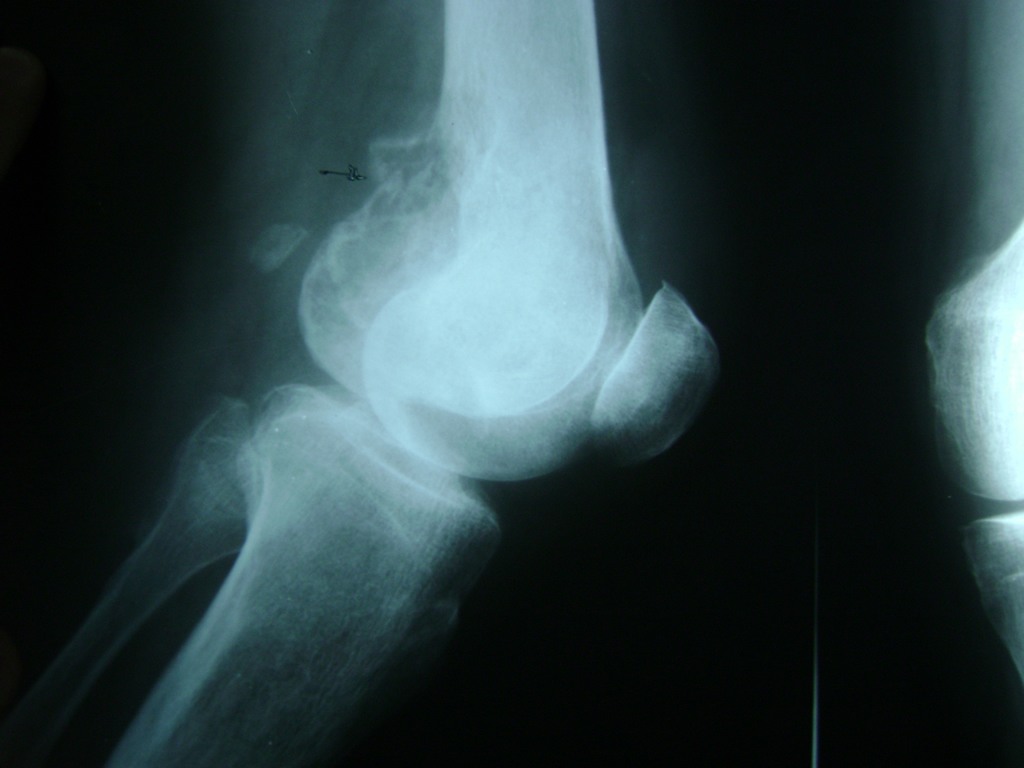

Cirugías de Codo - Rodilla

La artroscopia de rodilla es un cirugía en el cual la estructura interna de la articulación es examinada ya sea para realizar un diagnostico o para realizar un tratamiento, este procedimiento se realiza utilizando un instrumento parecido a un pequeño tubo llamado artroscopio.